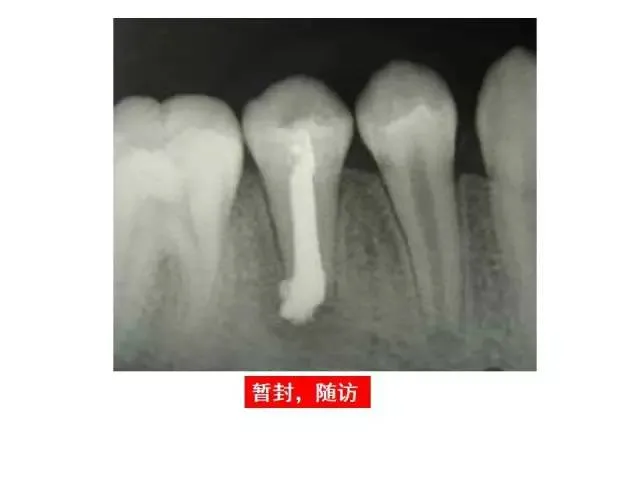

>PPT典藏 | 根尖诱导成型术

PPT典藏 | 根尖诱导成型术